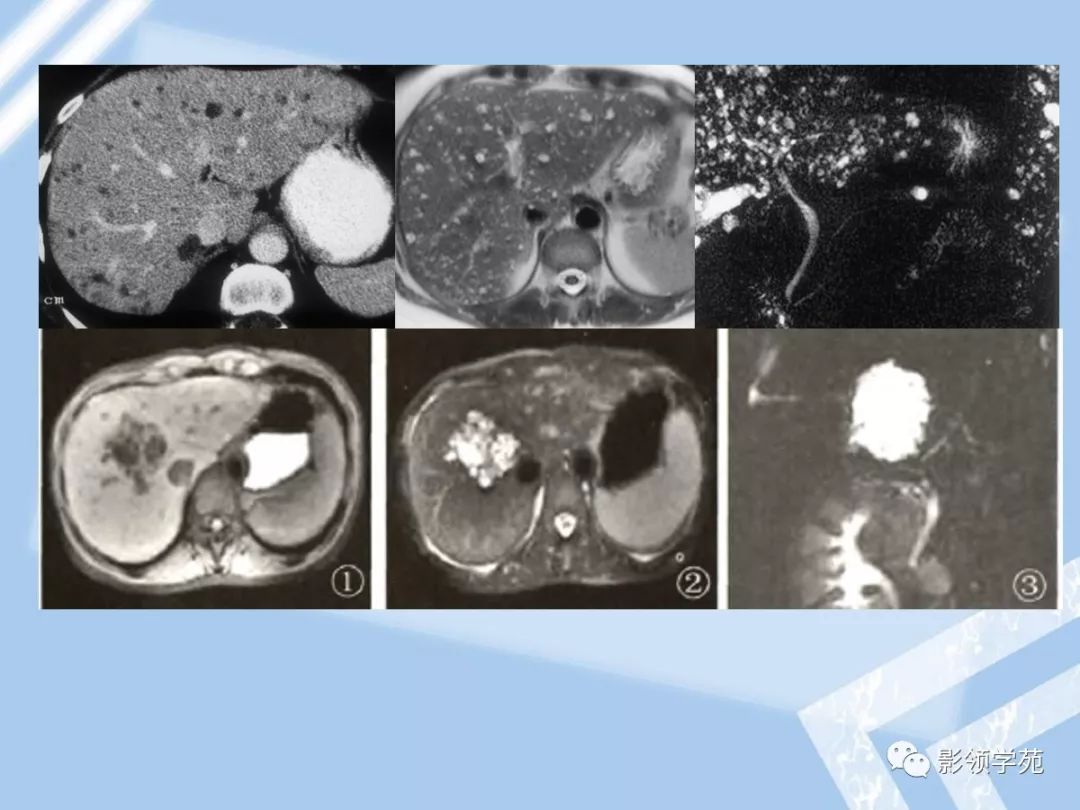

小儿肝脏间叶性错构瘤的mri表现影像天地

肝内胆管错构瘤ppt